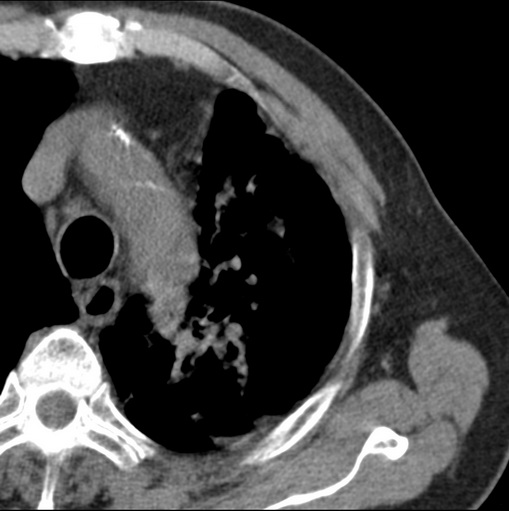

男性患者 81岁 咳嗽 咳痰 咯血

肿块贴近左肺门,包绕左上肺动脉,形态不规则。肿块增强扫描中度强化。纵膈内主动脉弓左旁间隙、气管隆突前、下间隙见多枚淋巴结影。综上考虑左侧中央型肺癌可能性大。图片没有完整上传,尤其是左肺上叶支气管分支层面没有上传,因此不好判断是叶支气管中断还是段支气管中断。另外,下图红色部分所示是“黏液支气管征”吗?